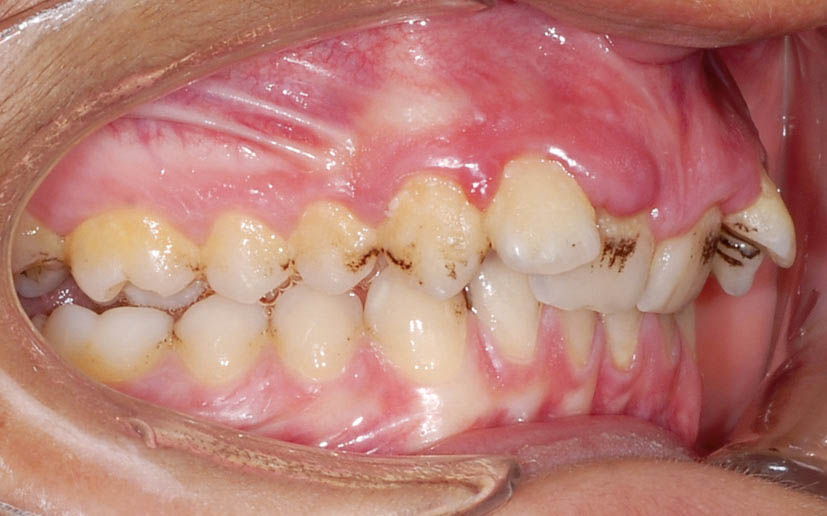

شکل 107-2: اکلوژن یک کاسپ کامل کلاسII در سمت راست

شکل 110-2: اکلوژن 5mm کلاسII

شکل 112-2: 3.5mm کلاسII در سمت راست